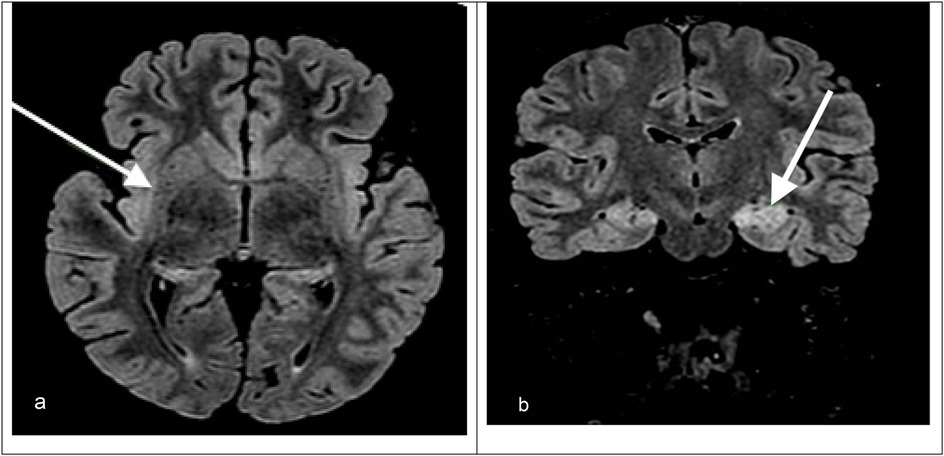

Upon admission to our hospital, a comprehensive examination was conducted, which included blood microbiological tests, metabolic and cerebrospinal fluid (CSF) analyses (including autoimmunity), and continuous electroencephalogram (cEEG) monitoring. he patient's condition gradually deteriorated, necessitating invasive ventilatory support. Continuous EEG monitoring showed an unstructured background tracing characterized by global slow large-amplitude activity. The monitoring registered almost continuous autonomic focal seizures with right EEG changes and subsequent generalization. Therapy was therefore initiated, which required the use of propofol, ketamine, phenytoin, and phenobarbital. After a second lumbar puncture (LP), intravenous steroids and immunoglobulins were also administered. A transitory reduction of seizure frequency was obtained only with high doses of the abovementioned antiepileptic drugs; however, cEEG recorded transitory BS patterns, with both right and left focal motor seizures and secondarily generalized seizures fulfilling the criteria for refractory SE. We decided to repeat an MRI, which showed hyperintensity signal alteration in the T2 FLAIR involving the hippocampus bilaterally (left > right) with concomitant alteration at the level of the claustrum (Figure 1).

Figure 1. (a) Axial T2-FLAIR MRI image showing hyperintensity in the right hippocampus and right claustrum (arrow). (b) Coronal T2-FLAIR MRI image showing bilateral hippocampal hyperintensities, which are more prominent on the left. The arrow indicates left hippocampal involvement.

MRI was repeated once during the PICU stay, showing non-specific signal alteration in the left hippocampus and left claustrum without signs of blood–brain barrier (BBB) disruption and resolution of the edema at the level of the corpus callosum, which was compatible with the hypothesis of an autoimmune condition (Figure 1).

MRI findings such as hyperintensities in the claustrum and hippocampi, particularly when bilateral, have been described in FIRES and may reflect seizure-induced or inflammatory injury (Figure 1). In particular, bilateral hippocampal and claustrum involvement has been associated with prolonged status epilepticus and may indicate underlying neuroinflammation (5). Although FIRES is a rare syndrome, several hundred cases have been reported in the literature. For example, the German FIRES registry alone includes 93 children (6), and multiple case series have been reported from Europe, Asia, and the Americas, with cohorts ranging from 12 to over 70 patients (4, 5, 7). The pathophysiology of FIRES is poorly understood. However, some evidence suggests an inflammatory condition involving the central nervous system, characterized by an increase in the levels of cytokines and chemokines in the CSF that exceed those observed in plasma (1, 2). To date, almost all cases reported in the literature describe an infectious episode with a non-specific influenza-like illness prior to SE onset; thus, FIRES may be considered a postinfectious immune system dysregulation that has a predilection for the central nervous system in young and healthy, yet vulnerable, individuals (2, 4). Preliminary evidence suggests that immunosuppressive treatments such as high-dose corticosteroids, intravenous immunoglobulins, plasma exchanges, and the more novel anakinra, a recombinant antagonist of IL-1 receptor, might be helpful, but their efficacy has not been confirmed (1, 2). Plasmapheresis was not performed in our patient because, at the time of clinical decision-making, the patient's EEG and imaging features were suggestive of an autoinflammatory rather than an autoimmune encephalitic process (i.e., typical of FIRES), and autoantibody results were still pending. Given the lack of specific evidence of an autoimmune cause, and based on current international recommendations (8), we prioritized the use of immunomodulatory therapy with corticosteroids, IVIG, anakinra, and a ketogenic diet. A summary of the decisional algorithm of refractory status epilepticus is illustrated in Figure 2. As the patient showed gradual clinical improvement following this multimodal approach, we did not escalate to plasmapheresis. Plasmapheresis could still be considered an option within the first 72 h, but it should not delay subsequent steps.